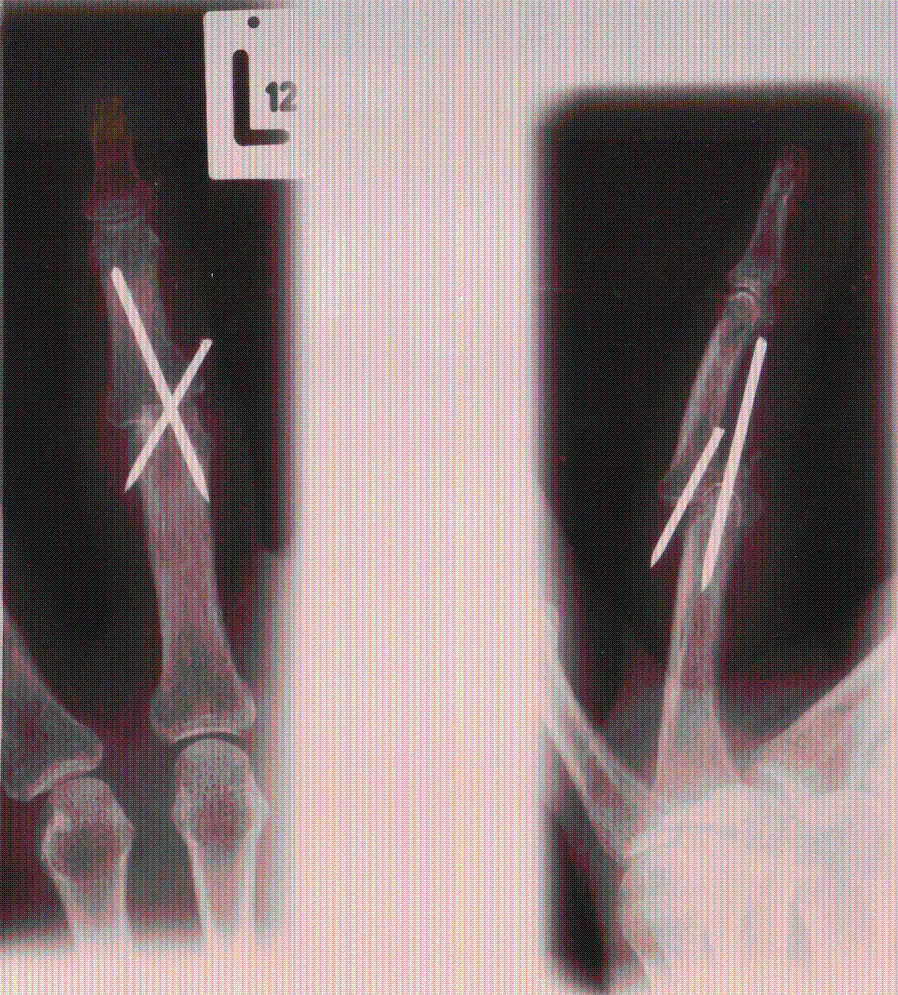

Die Unfallröntgenaufnahme zeigt eine Mittelgliedbasisfraktur des 4. Finger links mit Luxation des Hauptfragmentes und seiner Gelenkfläche nach dorsal

Bild110

Die postoperative Röntgenaufnahme zeigt gegenüber der Unfallröntgenaufnahme eine unverändert schlechte Stellung im Bereich der Luxationsfraktur.